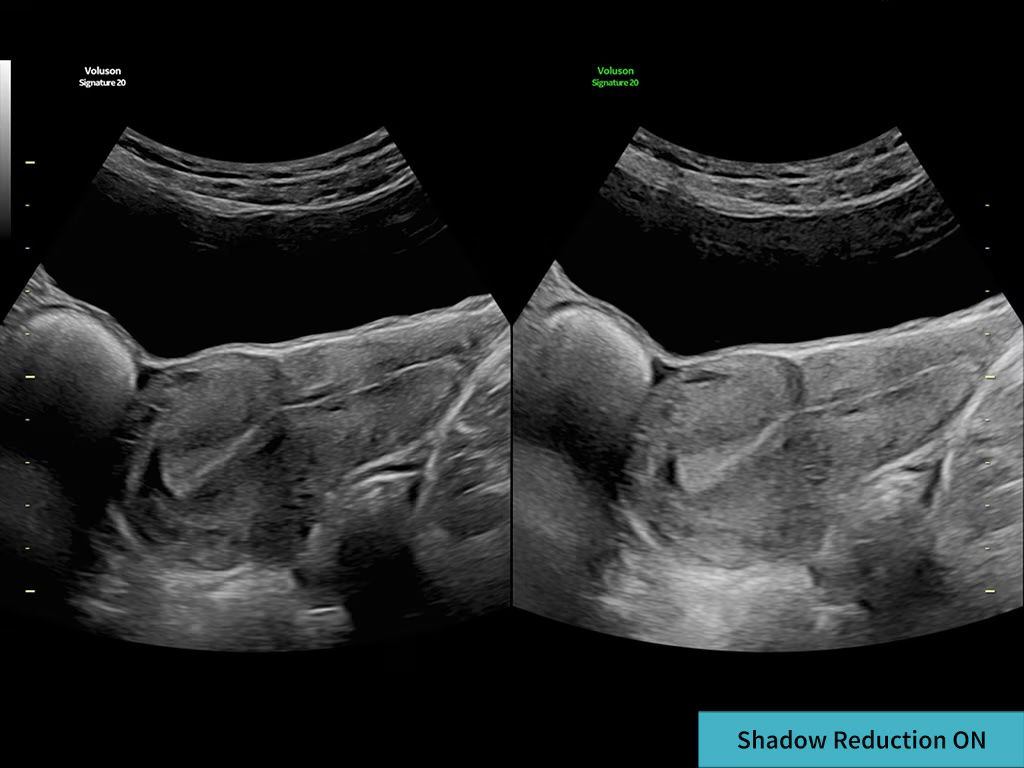

Decreases shadows on B-mode imaging which can obscure adjacent structures by helping to restore tissue information and borders.